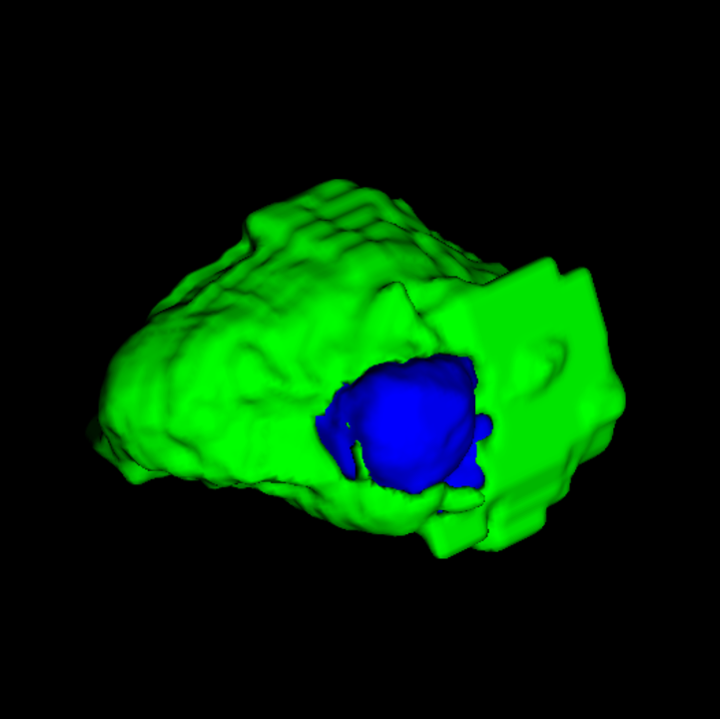

| Input | 3D Tumour | |||

![]() |

|||

Tumour Information Preservation. For the brain tumor segmentation, we use a Swin UNETR model[28, 70], trained with random rotation, and intensity as data augmentation. On the test set with human ground-truth annotations (), the brain volumes generated from single slice input preserve the volume of the different tumour components (paired t-test, for all 3 classes). In Figure 4, we highlight the tumor profiles of the generated MRIs compared to the ground truth tumour profile. The real MRI Dice score in the test set is 85.15 while the generated MRIs from a single slice have a dice score of 83.09. This shows how the generated MRIs indeed preserve the tumor information and can act as an affordable and informative pseudo-MRI, before conducting an actual costly MRI examination in hospitals. More detailed results are provided in supplementary material.